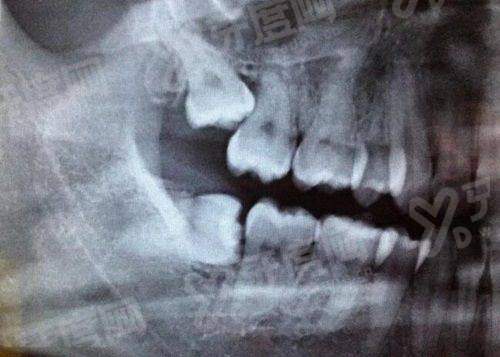

1、承德玥莱美口腔引进数字化口腔CT设备,能够清晰呈现牙槽骨密度、牙根形态等细节,为种植牙、复杂牙拔除等项目提供精细的影像支持,医生可根据三维重建图像制定个性化诊疗方案,提高手术成功几率。